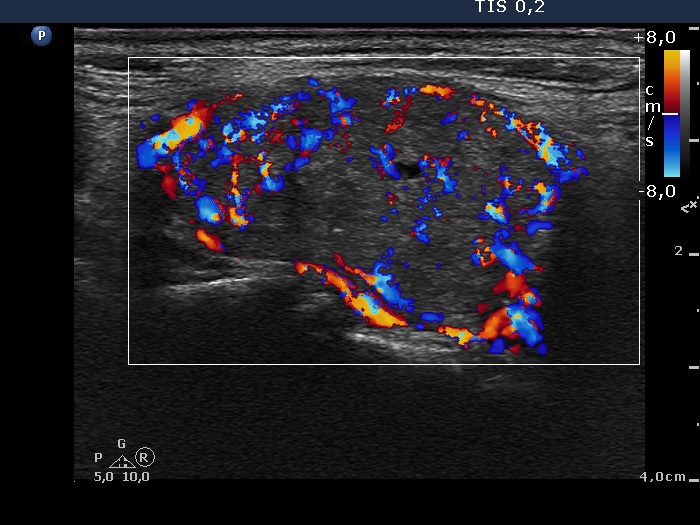

Ultrasonography: the thyroids were moderately hypoechogenic and contained several discrete, circumscribed lesions. There was a hyperechogenic nodule in the lower part of the right lobe while a cystic nodule in the upper part of the left lobe.

The thyroid is hypoechogenic and is surrounded with a relatively thin echonormal rim. This makes an appearance if both lobes were composed of a large hypoechogenic nodule. However, the echonormal rim corresponds to thickened connective tissue; a frequent phenomenon in an operated thyroid.

The upper part of the right lobe seems to be nodular, i.e. composed of two nodules at first sight. However, an insertion of the connective tissue and an acoustic shadow of a coarse calcification divides this part of the thyroid to two lesions. These do not fit nodules in a pathological sense.